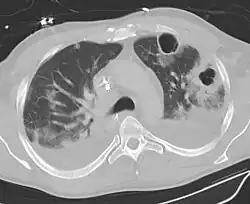

| Computed tomography (CT) scan of chest showing bilateral pneumonia with abscesses, effusions, and caverns. 37-year-old male. | |

A subpleural abscess.